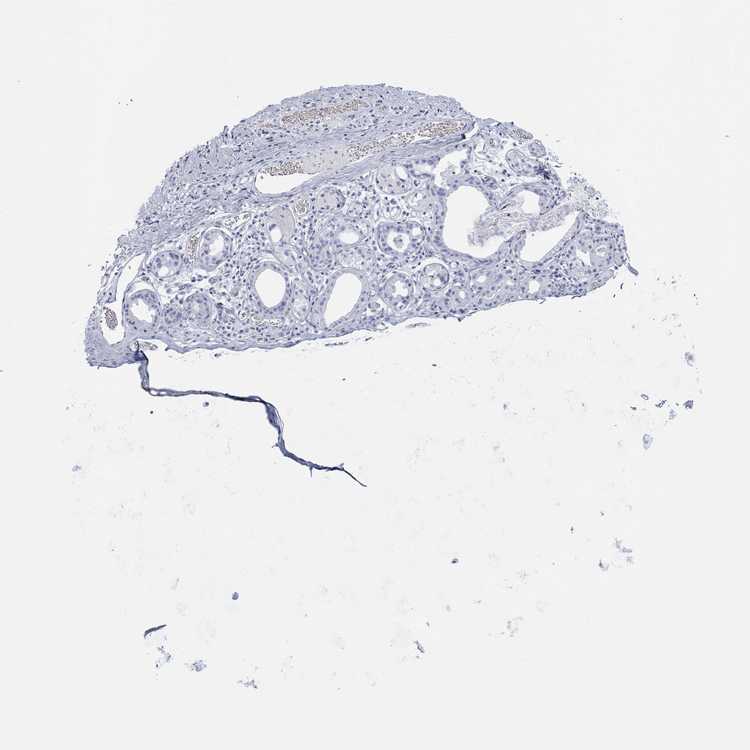

SOFT TISSUE 1 - Antibody stainingi

Antibody staining in the annotated cell types in the current human tissue is reported as not detected, low, medium, or high, based on conventional immunohistochemistry profiling in selected tissues. This score is based on the combination of the staining intensity and fraction of stained cells.

Each image is clickable and will lead to virtual microscopy that enables deeper exploration of all samples and also displays staining intensity scores, fraction scores and subcellular localization as well as patient and tissue information for each sample.

Antibody HPA023099Antibody HPA056734Antibody CAB002138

Chondrocytes -Not detectedNot detected

Fibroblasts Not detectedNot detectedNot detected

Peripheral nerve --Not detected